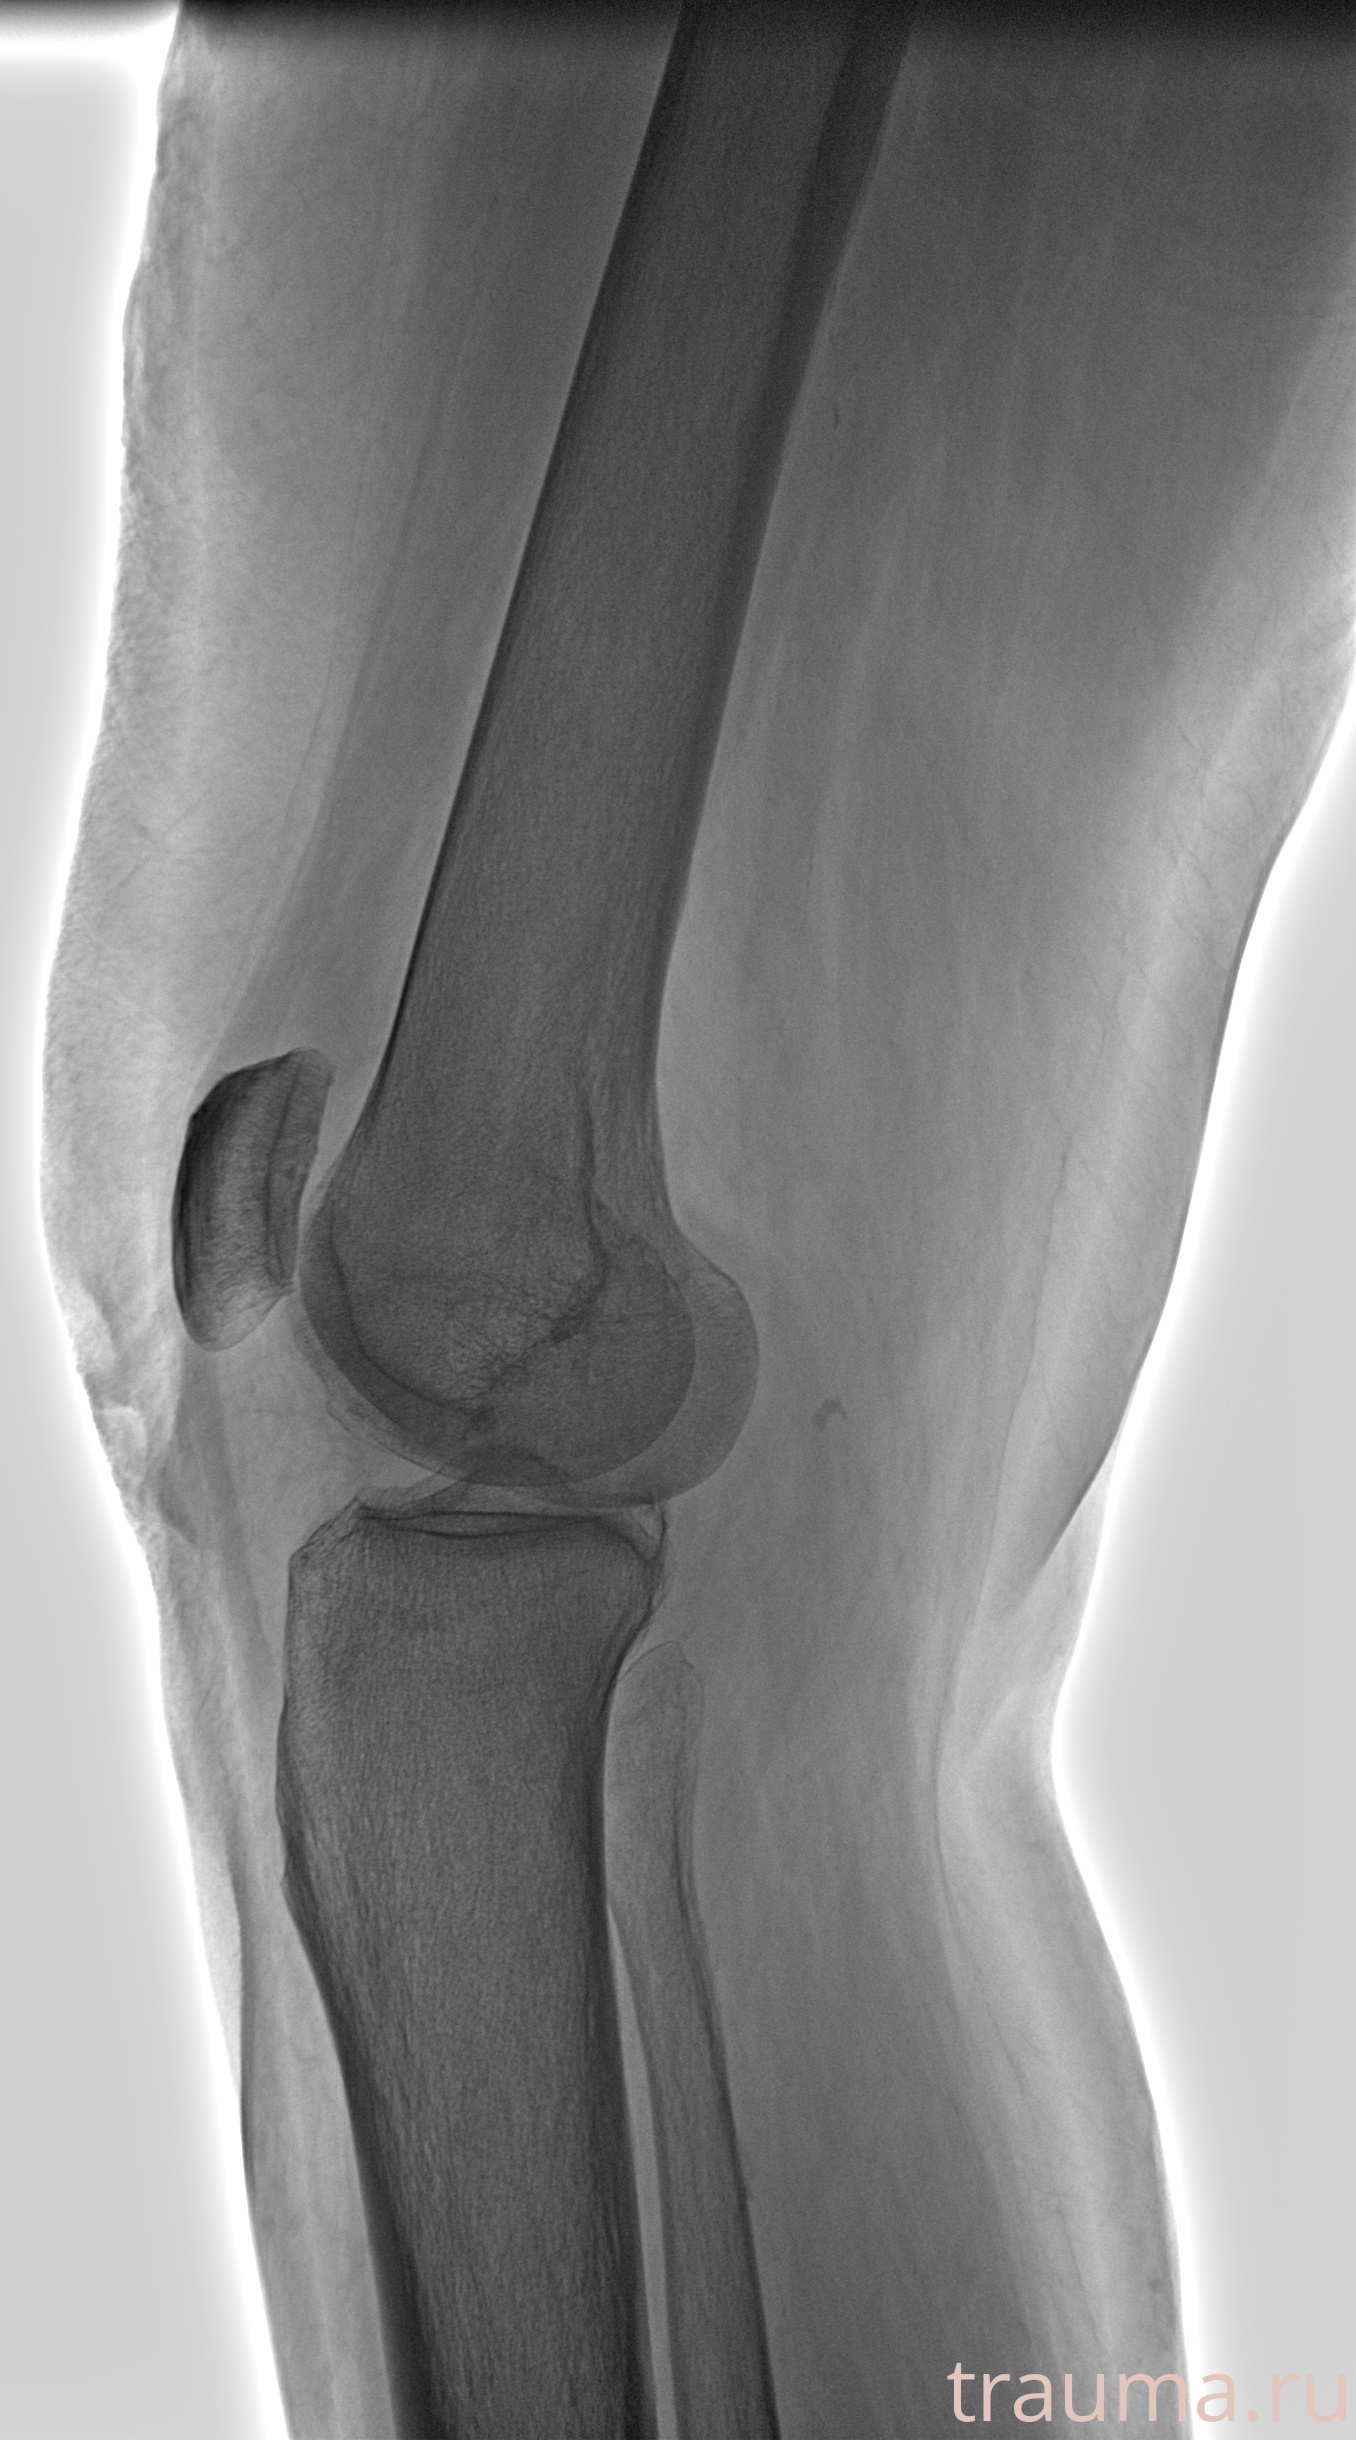

Рентгенограммы

Рентген на дому: по вашему адресу приезжает врач-рентгенолог, травматолог-ортопед с мобильным рентгеновским аппаратом, проводит диагностику травмы или заболевания, делает необходимые рентгенограммы, дает рекомендации по дальнейшему лечению. Получить качественные снимки в домашних условиях возможно благодаря уникальной методике, разработанной МосРентген Центром для института  Склифосовского